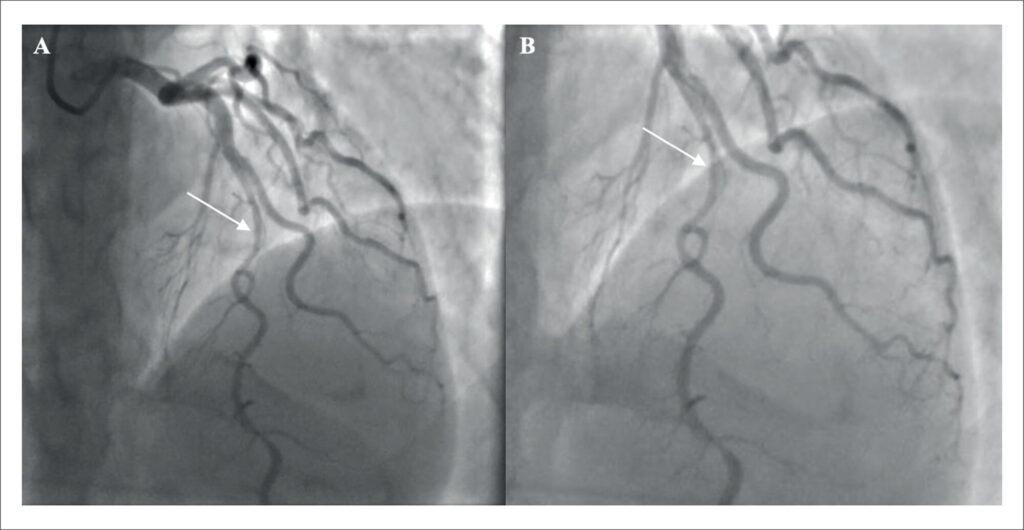

Coronary Artery Dissection Following Pharmacologic Stress Echocardiography and the Follow-Up of Clinical Management: A Case Report

Spontaneous coronary artery dissection (SCAD) remains a diagnostic and therapeutic challenge in the evaluation of chest pain. Misinterpretation of symptom characteristics and failure to consider the patient’s epidemiological profile may lead to inappropriate diagnostic workups and treatment strategies. The case described herein represents only the second report with similar characteristics published in major medical databases. This case underscores the importance of considering uncommon causes of chest pain and acute coronary syndrome (ACS), while also providing a brief review of relevant literature. The report was prepared in accordance with the CAse REport (CARE) guidelines.